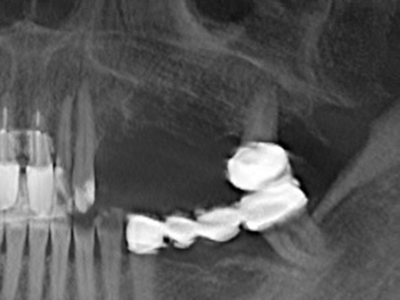

Фиг. 15: Прегледът на рентгеновата снимка след 1 година показва стабилно състояние на нивото на костта.